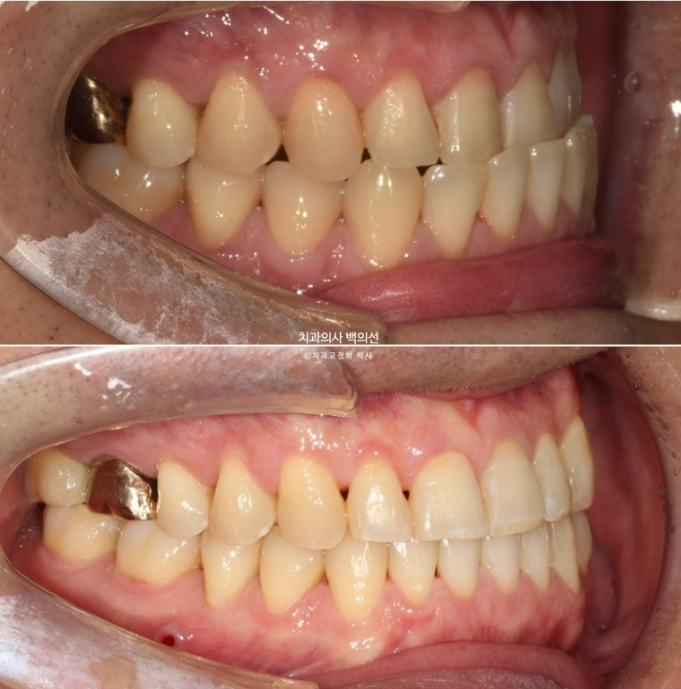

24.10

교정용 나사인 미니스크류를 아래쪽에 2개 심고 3급 고무줄을 걸며 치료를 진행중입니다.

치료시작 10개월차 첫세트의 장치를 모두 낀 후 모습입니다.

큰 공사는 끝났으나 미진한 부분들이 보입니다.

앞니 반대교합은 해결 되었으나 여전히 중심선이 미세하게 안 맞고

어금니 교합이 뜨는 부분이 있어 24년 10월 재제작에 들어갔습니다.